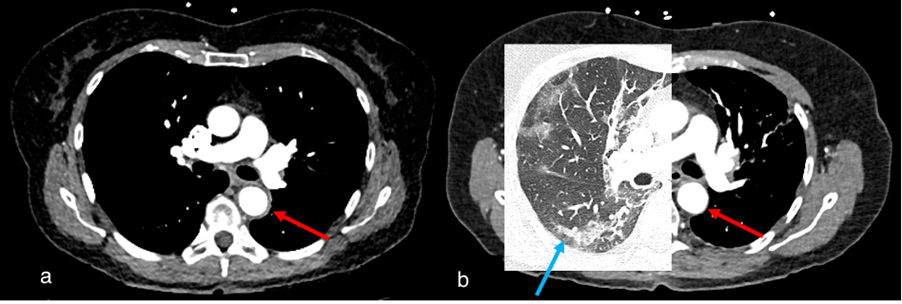

Figure 5.

Case 2, 60-year-old female. (a) Initial chest CT to clarify pulmonary embolism or COVID-19 findings showed pneumonic infiltrates of indeterminate appearance for COVID-19 (blue arrow) and revealed a large mediastinal mass (red arrow). (b) PET/CT demonstrated mild FDG-uptake, making the diagnosis of thymoma more likely than lymphoma.